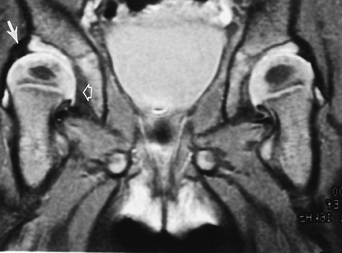

![]() |

FIGURE 4-49 MR image in the frog-leg position shows dislocation of the left hip (arrow).

FIGURE 4-50 Coronal T2-weighted image with developmental hip dysplasia on the right. The medial joint space is widened (open arrow). The labrum is well demonstrated (arrow), and the femoral head is less well covered compared with the left hip.